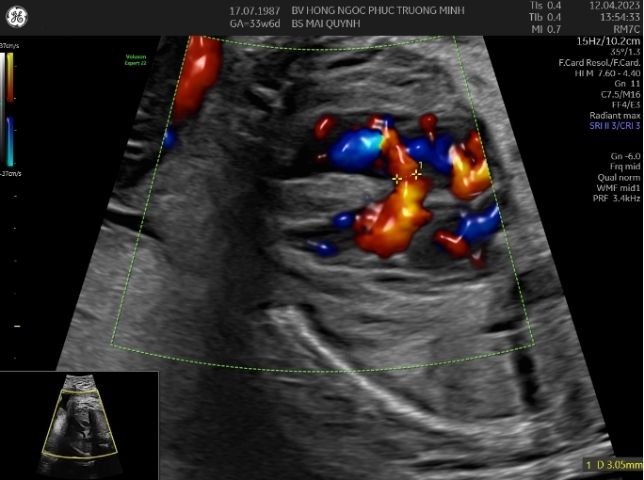

Hình ảnh thông liên thất ở thai 30 tuần với kĩ thuật 4D STIC tim thai.Siêu âm tim thai là một kỹ thuật chuyên sâu, ngoài kiến thức, kinh nghiệm và trình độ chuyên môn của các bác sĩ, trang thiết bị cũng là một phần rất quan trọng. Hiện nay, khoa Sản Phụ khoa - Bệnh viện Đa khoa Hồng Ngọc Phúc Trường Minh là cơ sở đầu tiên và duy nhất trên cả nước sở hữu máy siêu âm hiện đại nhất thế giới - Voluson Expert 22 của hãng GE Healthcare. Với công nghệ UltraHD, Augment, Shadow Reduction.... cùng các kĩ thuật tái tạo tim 3D, 4D STIC cho phép tăng độ chính xác trong chẩn đoán bất thường tim thai cũng như minh họa cho cha mẹ hình ảnh thai nhi một cách sinh động và trực quan nhất có thể.